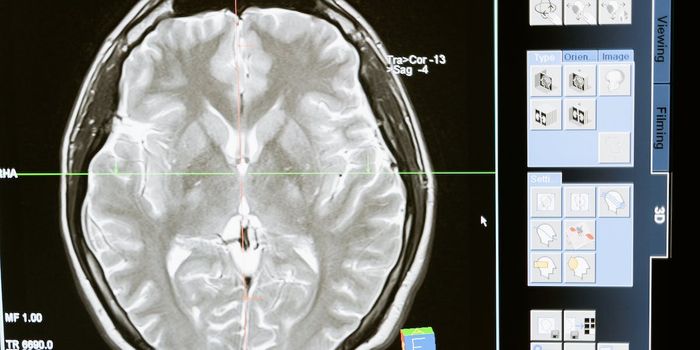

SEP 02, 2024NeuroscienceType 2 diabetes and prediabetes are linked to faster brain aging. Healthy lifestyle habits may protect against this effe ...

JUN 09, 2024NeuroscienceResearchers developed a method to predict dementia with over 80% accuracy up to nine years before diagnosis using fMrI s ...